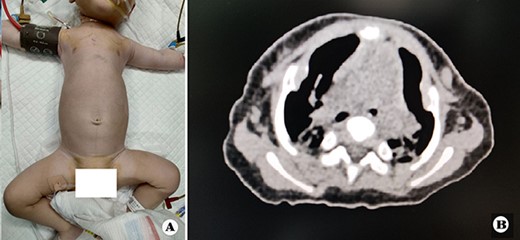

The patient was a female infant born at term with no family history. After birth, the patient developed cyanosis and dyspnea immediately, and emergency intubation and ventilation were performed. One week later, she was weaned and oxygen was given with mask. Oxygen saturation could be maintained basically, but it would decrease when eating and crying. She was eventually diagnosed as ATD and admitted to our hospital to accept surgery four months after birth. Physical examination showed that her chest circumference was 35 cm, and her thorax was narrow and small (Fig. 1A). CT scan revealed that her thorax was deformed, the lateral chest walls were slightly sunken and the lung compression was obvious (Fig. 1B). The operation was performed under general anesthesia. Midsternotomy was made. After the two sternal halves were expanded, three steel bars were placed and fixed on the anterior surface of the sternum (Fig. 2A and B). The bars were covered with pectoralis major muscles, and the skin incision was eventually sutured (Fig. 3A). The chest circumference increased to 40 cm, and the respiratory function was significantly improved postoperatively. Mechanical ventilation was continuously used for 3 days after operation. After weaning, the mask was used for intermittent oxygen supply and stopped 35 days after operation, with the oxygen saturation maintaining above 91%. The patient was discharged 41 days postoperatively. She was followed up for 3 months. There was no hypoxia when calm, but mild hypoxia when crying, which would be relieved after quiet. CT examination 3 months after operation showed that the shape of thorax is improved (Fig. 3B).

(A) Thorax appearance before operation, and (B) CT scan image of thorax before operation.